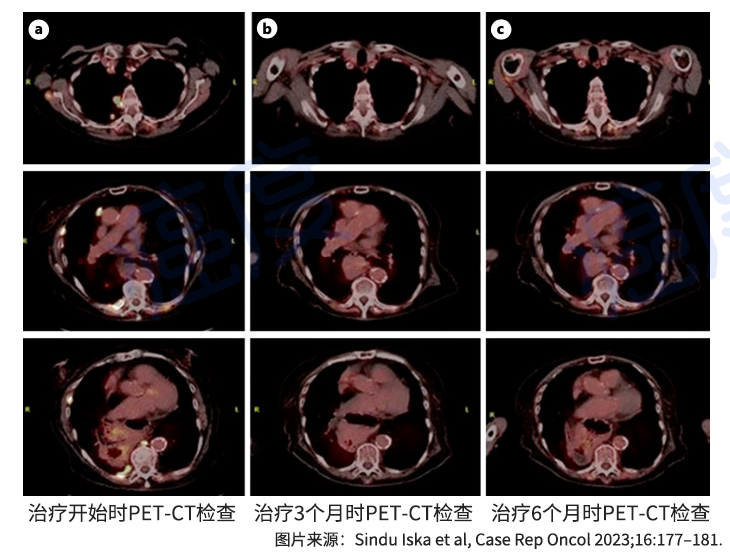

治疗三个月后,PET-CT影像学检查显示病灶已经消失,达到完全缓解。也就是说,所有影像学检查都看不到肿瘤病灶了。治疗六个月后,PET-CT检查仍然显示病情稳定。目前,她仍在接受AMG510的靶向治疗,耐受性良好,生活质量与患病前相比没有什么变化。

治疗不同时期PET-CT的检查